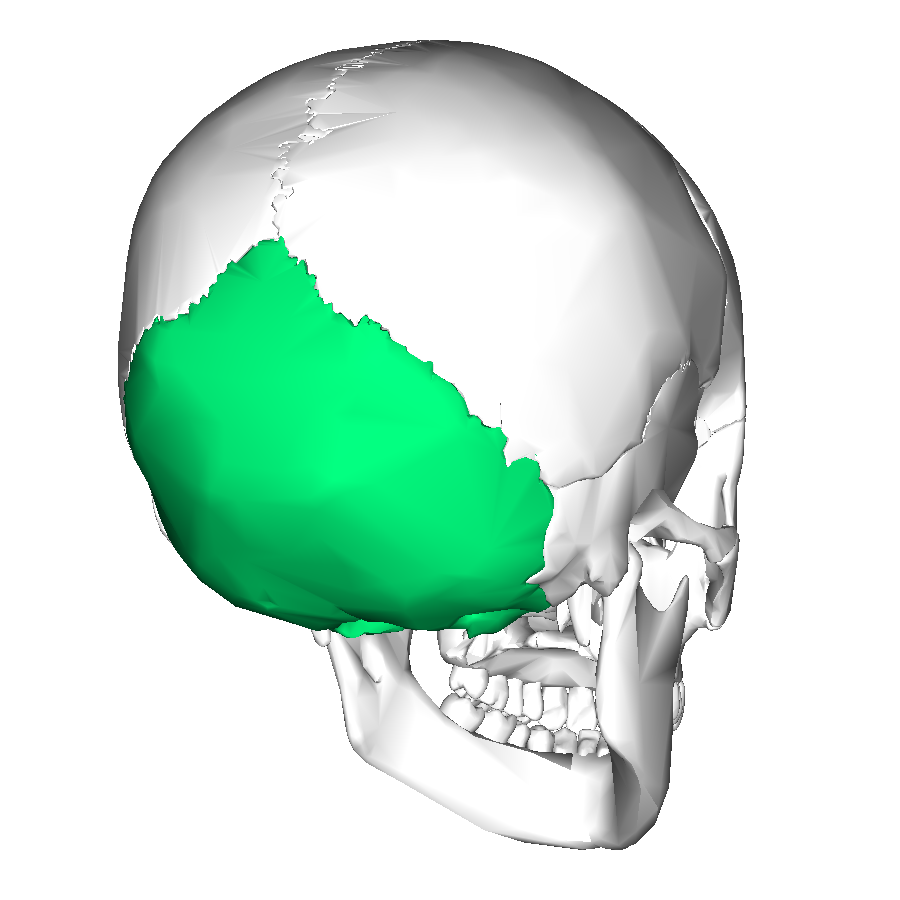

Africanus schrieb:Meine Abbildung zeigt, an welcher Stelle des Schädels der "occipital bone" tatsächlich liegt, während Deine Abbildung den Anschein entstehen lässt, dass dieser höher am Schädel liege. Das nenne ich manipulativ.

Africanus schrieb:Meine Abbildung zeigt, an welcher Stelle des Schädels der "occipital bone" tatsächlich liegt, während Deine Abbildung den Anschein entstehen lässt, dass dieser höher am Schädel liege. Das nenne ich manipulativ.

Deine Quelle:

Wikipedia: Occipital bonevon derselben Quelle.

Vergleiche mit meinem Bild- es gibt keinen Unterschied:

Original anzeigen (0,2 MB)

Original anzeigen (0,2 MB)Dein Manipulationsvorwurf ist also einfach nur lächerlich. Vielleicht lebst du in einer Welt in der zwei räumliche Dimensionen existieren und kannst Darstellungen dreidimensionaler Objekte aus verschiedenen Perspektiven nicht verstehen?

Mach dich nicht lächerlich- wenn es um Perspektive geht, passt meine Darstellung besser zu den Hinterkopffotos als deine.

Ich dachte es würde dich freuen- schließlich ist im Autopsiebericht von der Eintrittswunde im occipitalen Knochen die Rede!